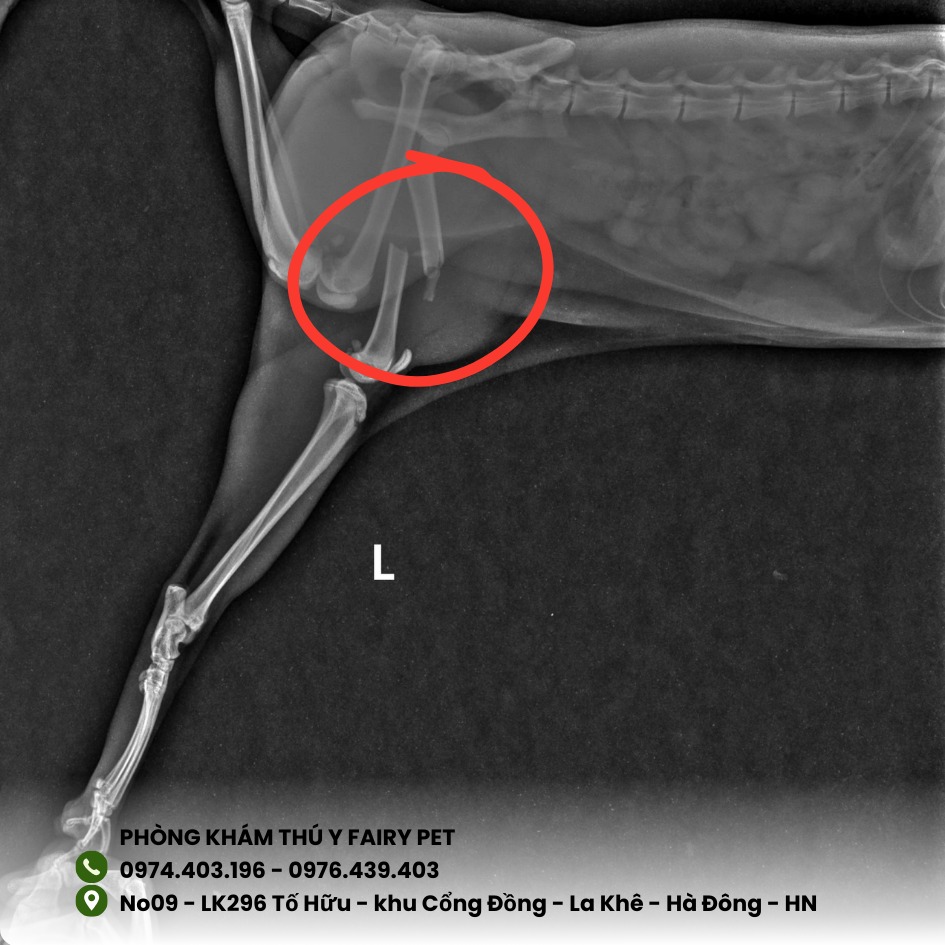

Khi chẳng may thú cưng bị 𝒈𝒂̃𝒚 𝒙𝒖̛𝒐̛𝒏𝒈 khiến nhiều Sen lo lắng.

👉 Thông thường, với chó mèo, thời gian lành xương dao động 3–8 tuần tùy theo vị trí gãy, độ tuổi và cách chăm sóc sau điều trị.

🩻 𝑪𝒉𝒂̂̉𝒏 đ𝒐𝒂́𝒏 chính xác 𝒃𝒂̆̀𝒏𝒈 𝑿-𝒒𝒖𝒂𝒏𝒈

✅ Chụp X-quang – xác định chính xác tình trạng gãy xương